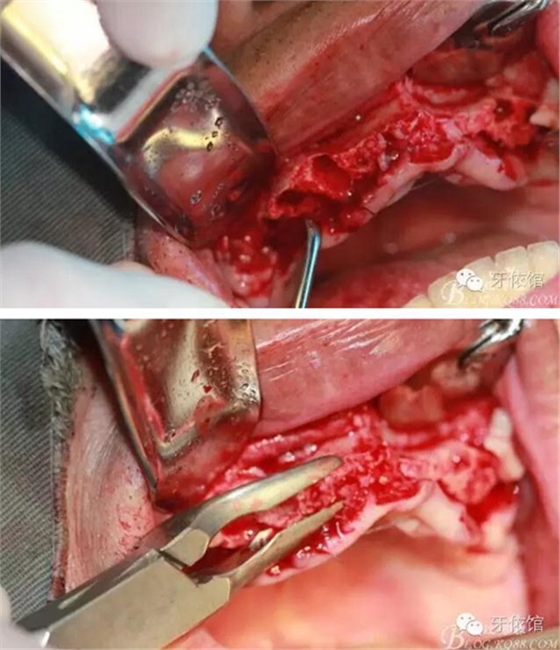

這個角度看1,2牙位骨寬度是不是很???僅2mm

用擴(kuò)孔鉆去除切牙孔內(nèi)神經(jīng)纖維和血管

降低骨高度,左右1,2骨寬度嚴(yán)重不足,決定將前牙2——2區(qū)間植體植在切牙孔內(nèi)